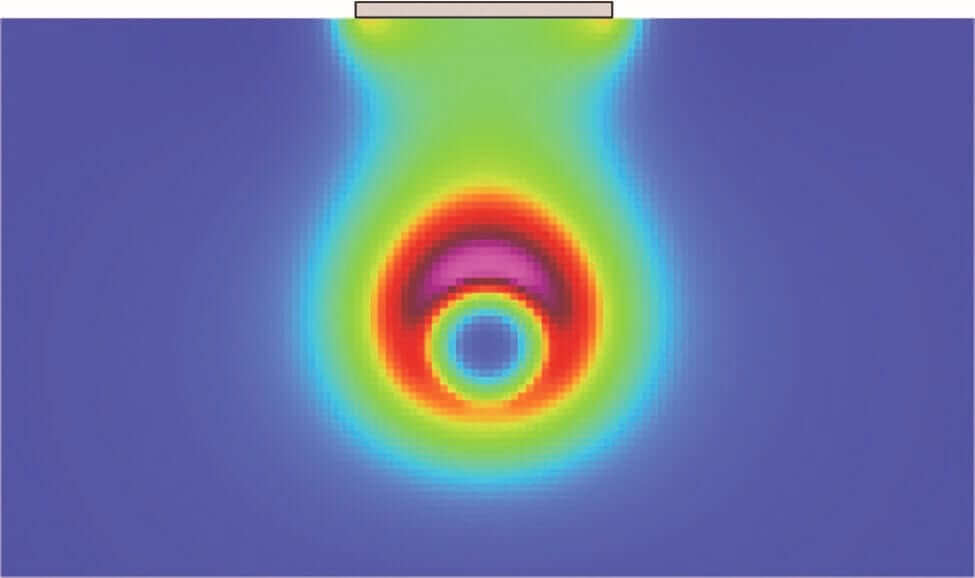

RFAL uses bipolar radiofrequency energy that has a controlled path. This makes the radio energy travel in a precise and efficient way that will increase patient safety and results of the procedure. The radio energy will heat up and tighten the skin at the same time as it destroys the fat deposits. Radio Frequency Lipo is the new medical sensation!